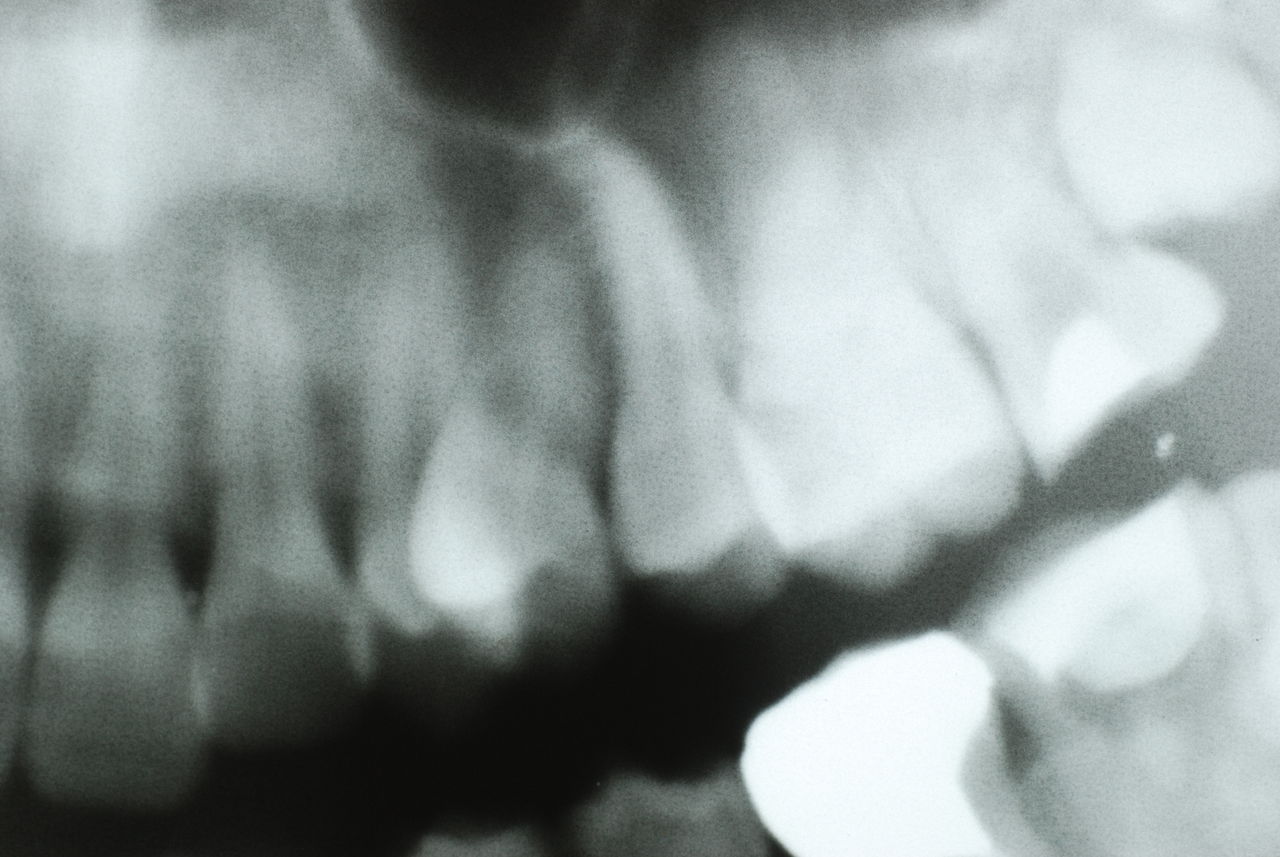

左下の歯は歯の中の治療も?ですごい歯周病を患い歯茎の穴(ポケットと呼ばれるところ)から膿が出ているのです。ばい菌と毒素で骨が溶けて深い穴ができてそこにまたバイキンと毒素がたまるという悪循環ができているのですね。

抜きたくないと抵抗されてもこのような歯が生き返ることもないし、噛む度にバイキンを血管に押し込み血管の中にバイキンを押し込む菌血漿を起こしていますから、動脈硬化や心臓、腎臓などの血管豊富な場所での病気(感染症)を起こしている可能性が高いのです。

右下の歯は歯の中の治療もあやしいのですが、金属と歯の間がすでに虫歯で崩壊し始めています。